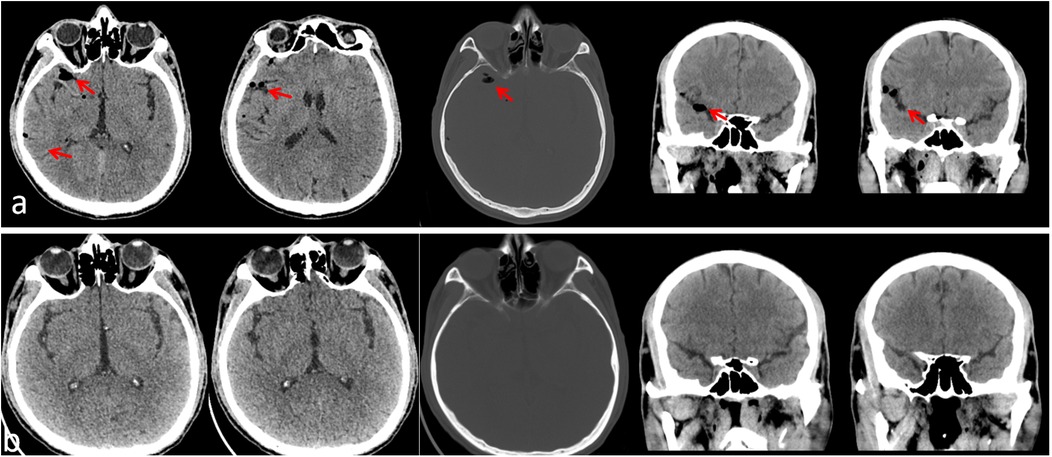

Unilateral Bioportal Endoscopy (UBE), as a minimally invasive technique, has shown significant advantages in the treatment of spinal disorders. However, it comes with surgical risks and complications, particularly acute neurological deficits. In this report, we present a rare case of pneumocephalus as a complication following unilateral dual-channel spinal surgery (UBE) for lumbar disc herniation. A 54-year-old male patient underwent UBE-assisted disc removal surgery for L5-S1 disc herniation. No obvious dural tear was noted during the surgery. Postoperatively, the patient experienced difficulty awakening from anesthesia, with signs of altered consciousness. CT imaging revealed pneumocephalus. On the second postoperative day, cerebrospinal fluid leakage and symptoms of decreased intracranial pressure were observed. After symptomatic treatment, no significant neurological sequelae were noted, and the patient was discharged. Postoperative clinical signs of increased intracranial pressure and imaging evidence of pneumocephalus suggest the occurrence of dural injury.